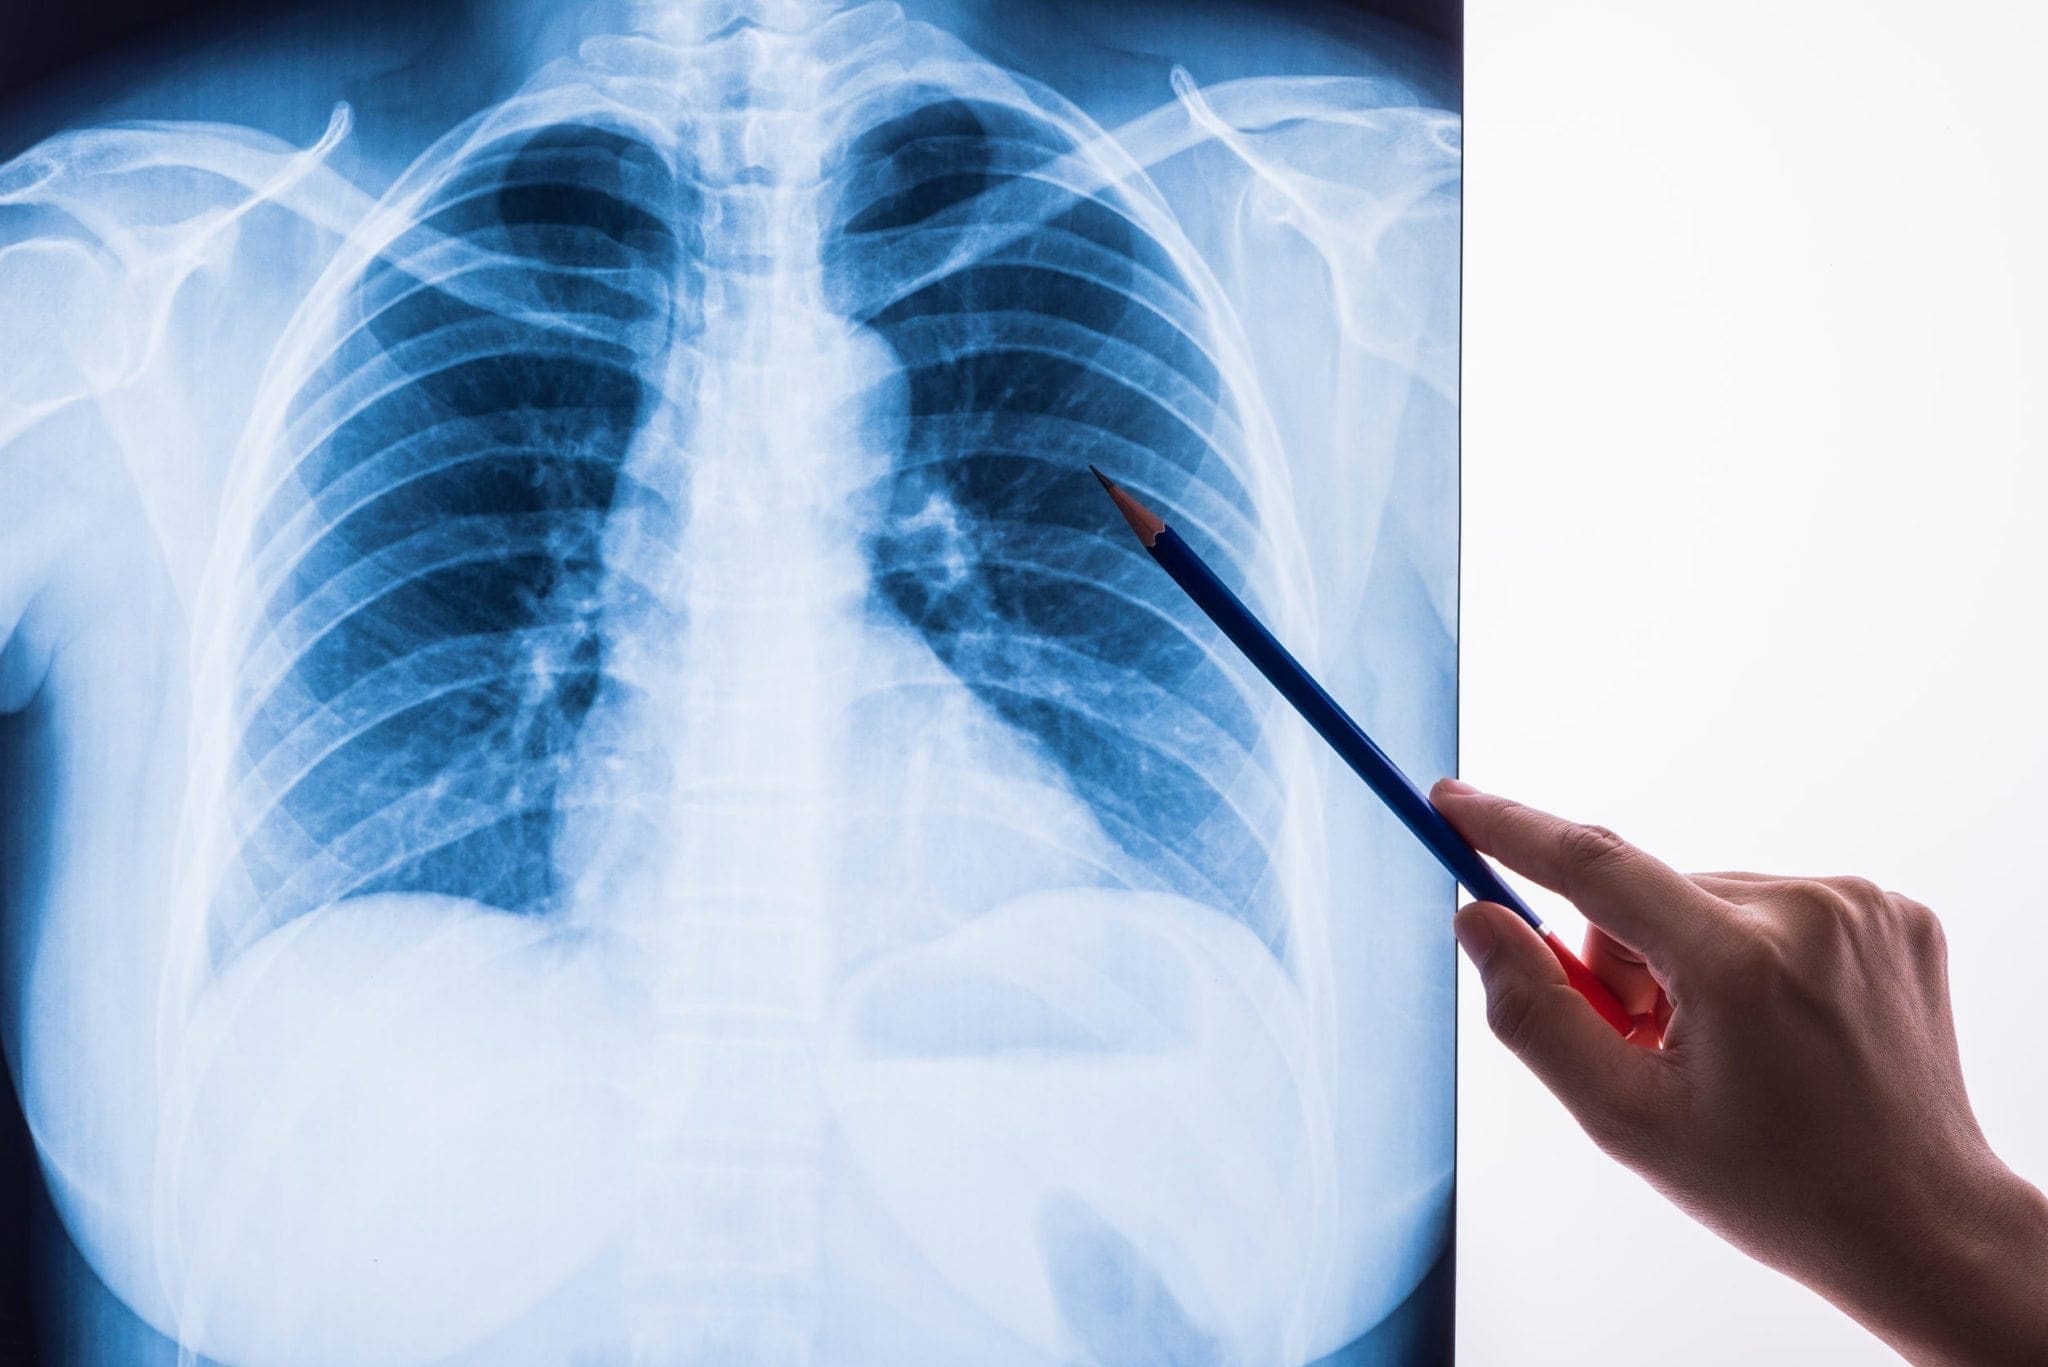

Пульмонология

Патология органов дыхания

Врач со снимком легких